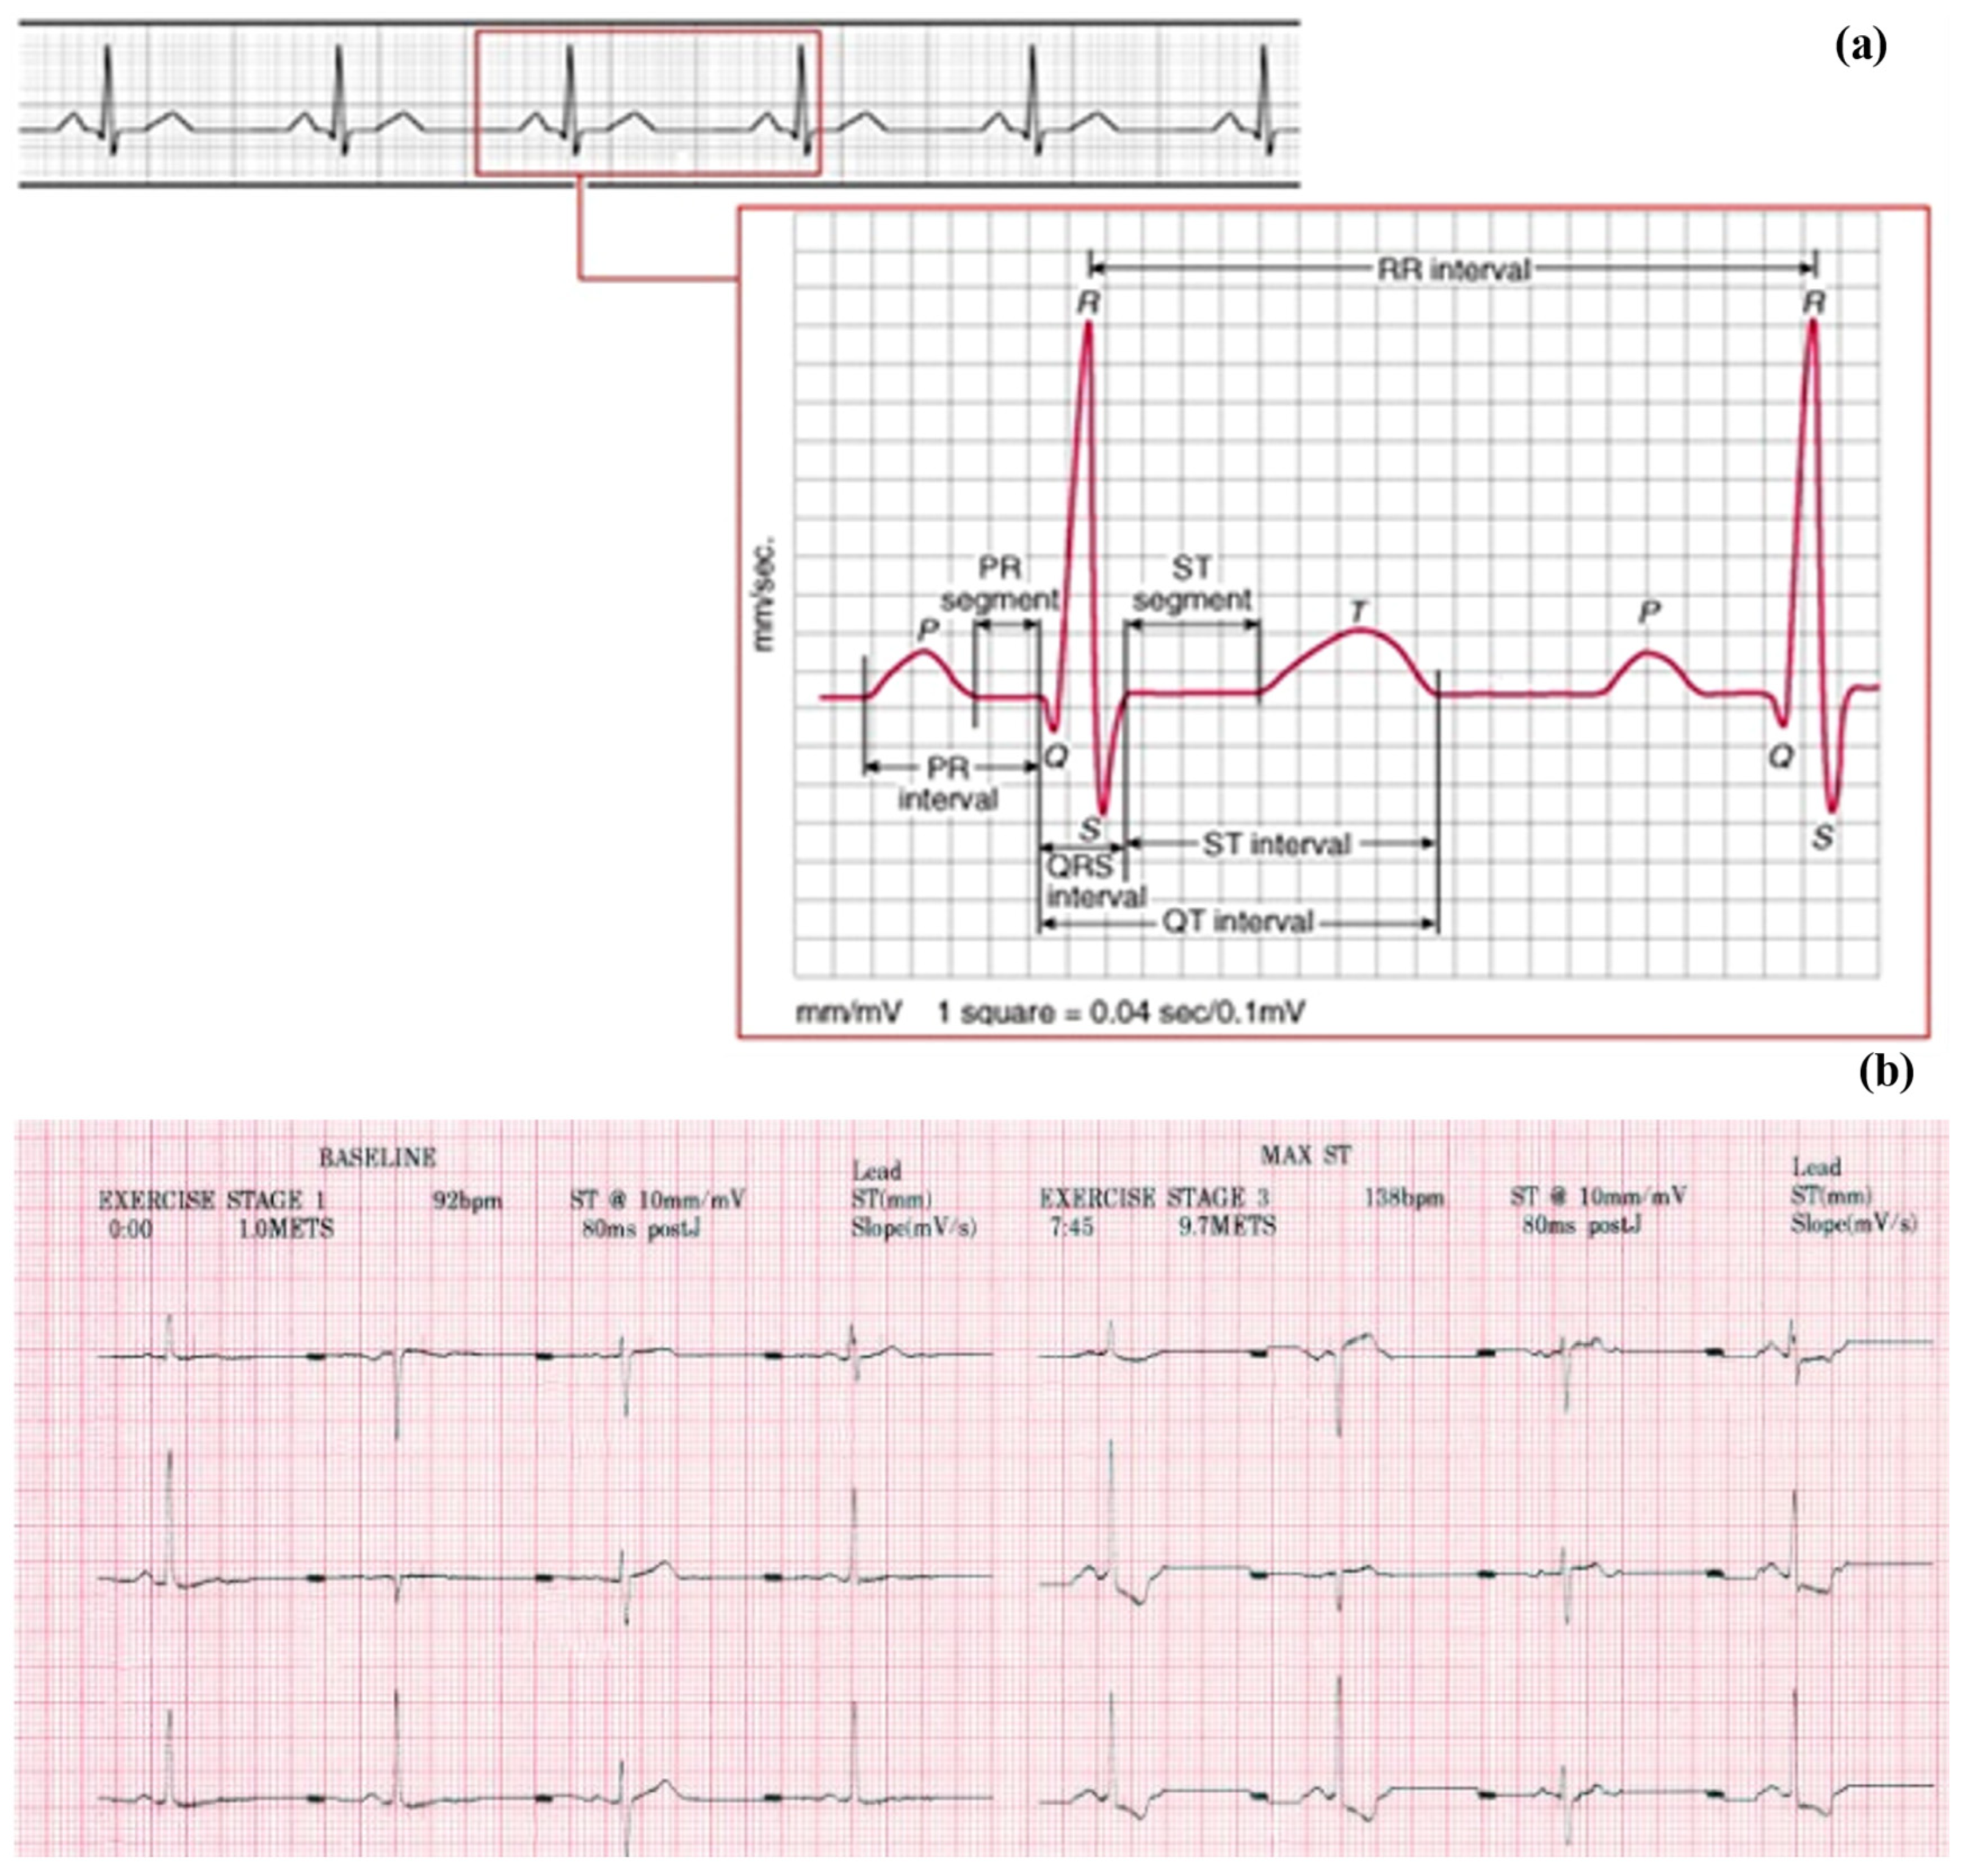

2.1. Dataset

2.2. Data Extraction

2.2.1. Image Scanning